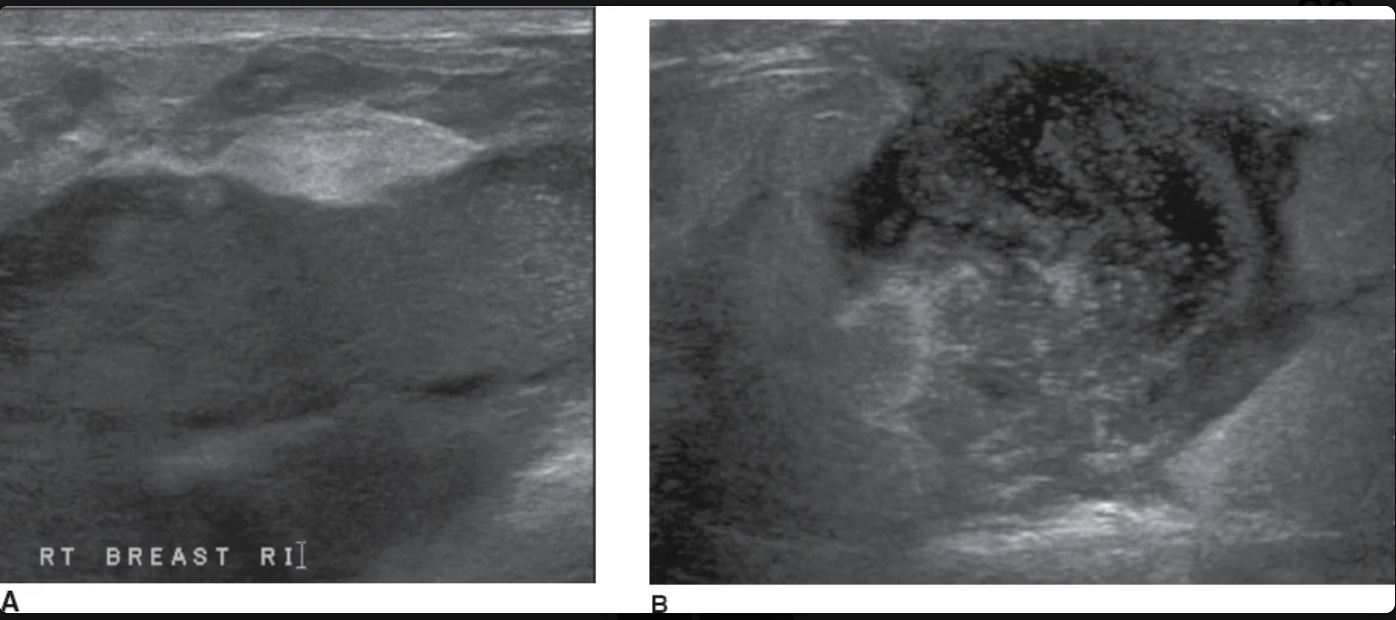

The masses in image were discovered in lactating patient who were suffering from focal breast erythema, swelling, fever, & rain. What is the most likely diagnosis

breast abscess

What lab would most likely be elevated in the patient with this image

White blood cell count